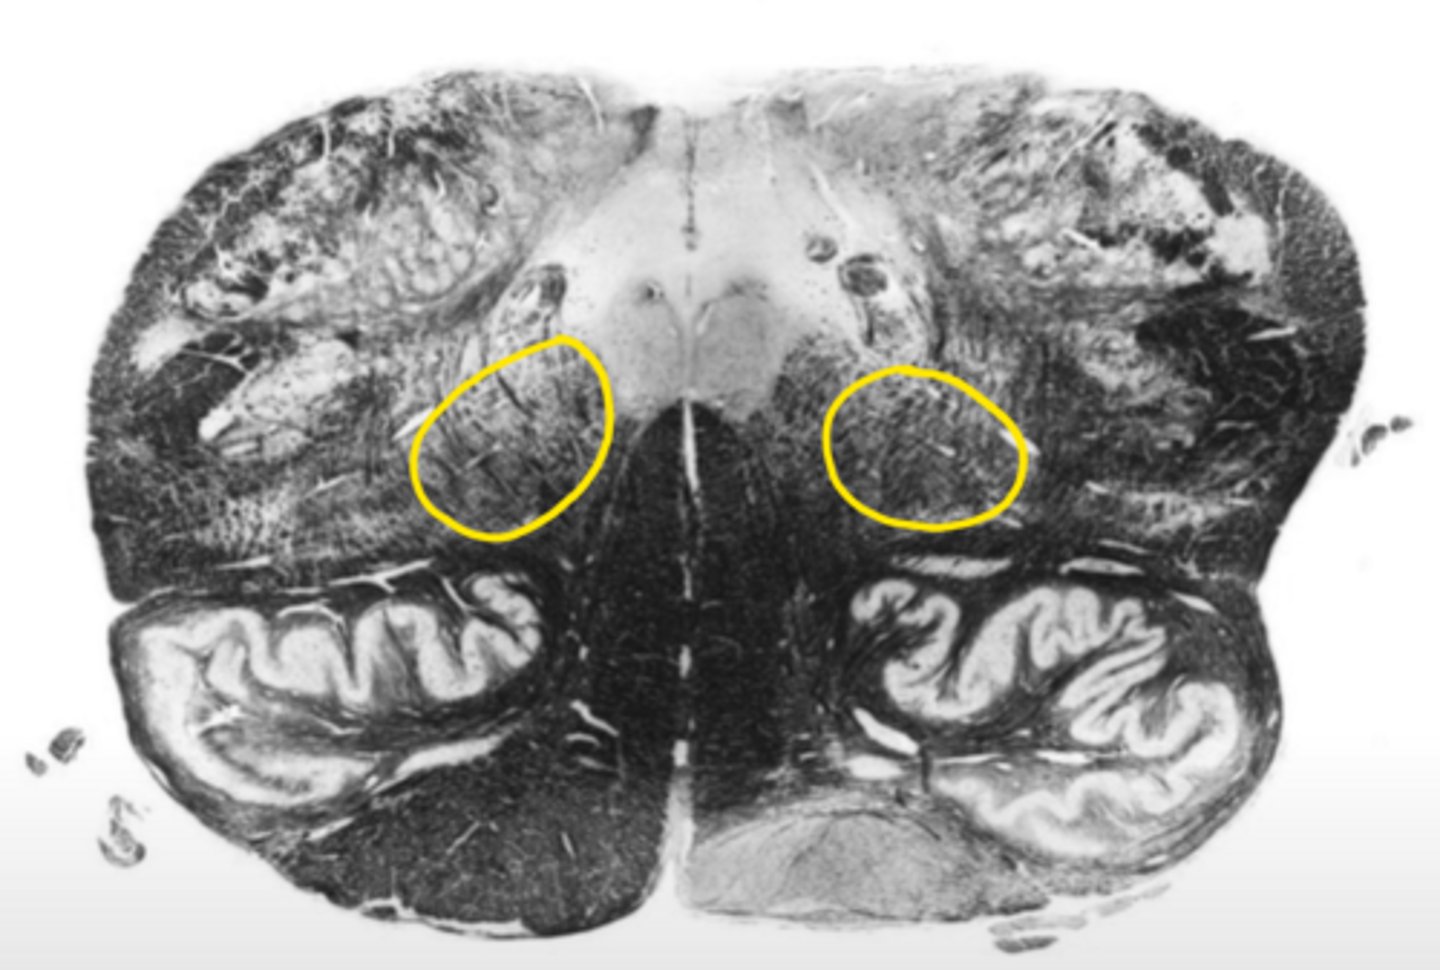

central canal

ID the space

central gray

ID the structure

hypoglossal nucleus

ID the nucleus

gracile nucleus

cuneate nucleus

inferior cerebellar peduncles

reticular formation

internal arcuate fibers

ID the fibers

principle olivary nucleus

medial lemniscus

corticospinal fibers

anterior median sulcus

closed medulla

ID the brainstem level